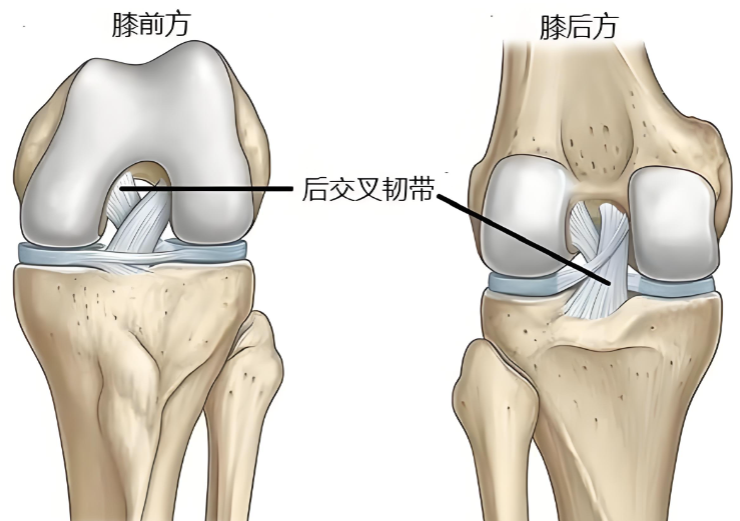

位置與結(jié)構(gòu)

后交叉韌帶位于膝關(guān)節(jié)最深部,起自股骨內(nèi)髁外側(cè)面前部,向后下方延伸,止于脛骨平臺(tái)后方斜坡。該韌帶比前交叉韌帶更粗大和強(qiáng)壯。

核心功能

后交叉韌帶的主要功能是抵抗脛骨后移,作為防止小腿骨相對(duì)于大腿骨向后錯(cuò)位的最主要結(jié)構(gòu),在上下坡、下樓梯和減速奔跑時(shí)起著關(guān)鍵的穩(wěn)定作用。